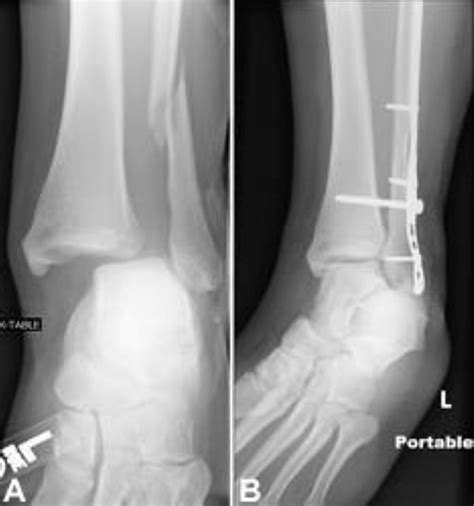

Diagnosing a Stress Fracture Ankle

Diagnosing a stress fracture ankle typically involves a combination of physical examination and imaging tests. A healthcare provider will:

• Order imaging tests such as X-rays, MRI, or bone scans to confirm the diagnosis.

Imaging tests are crucial because stress fractures may not be visible on initial X-rays. An MRI or bone scan can provide a more detailed view of the bone and surrounding tissues.

In some cases, surgery may be required to stabilize the fracture and promote healing. This is typically reserved for severe or non-healing fractures.